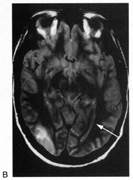

Fig. 15. Bilateral incomplete hemianopia. A 69-year-old man with decreased vision after prostate surgery. A. Fields show remaining central parafoveal vision with some sparing of inferior left quadrant. Note how the defect respects the vertical meridian. B. MRI shows bilateral medial occipital infarction, with sparing of the occipital poles, accounting for the macular-sparing bilaterally. (Courtesy of Dr. Lucia Vaina.)